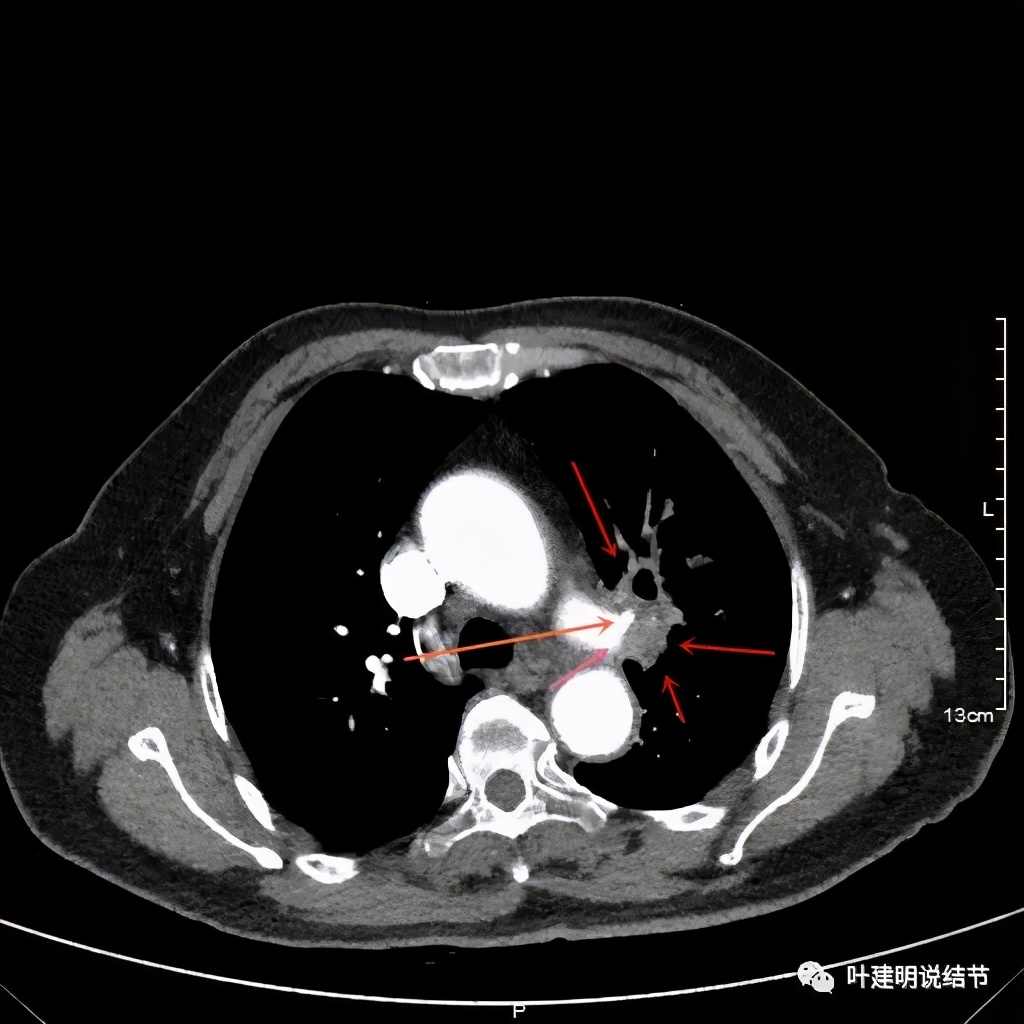

上图也示桔色箭头示左肺动脉分支处仍被软组织(原肿瘤所在)包绕,粉色箭头示肺动脉仍与肿瘤处关系密切

上图示肿瘤部位仍与肺动脉关系密切,似乎未能脱开,红色示肿瘤处